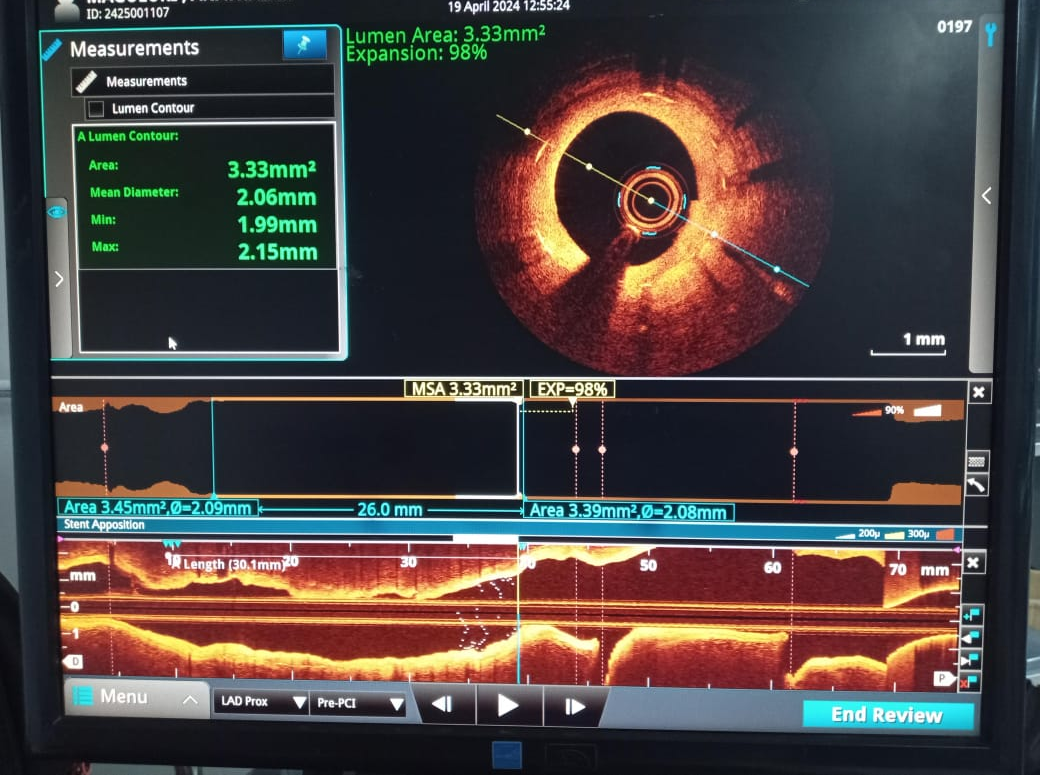

PCI was planned to LAD ISR lesion through right radial approach with 6 French sheath. Optical Coherence Tomography (OCT) was chosen for intracoronary imaging modality as it gives high resolution images to know the plaque morphology, exact mechanism of ISR which help in planning device selection and also to assess the adequacy of lesion preparation. 3.5 EBU 6 French Guiding catheter was taken with Runthrough (Terumo ,Japan) guidewire. Initial OCT ( Dragonfly OpStar catheter, Abbott,USA) run was done. Thick neointimal hyperplasia was seen with neoatheroma in mid portion of ISR lesion. mm as mean diameter in the distal reference segment was 2.9 mm (EEL to EEL) and the measured stent diameter was 2.6 mm. The MLA at the tightest point was 1.15 mm2 . Lesion length was 28 mm. We planned to do plaque modification with cutting balloon and correction of stent under expansion with non compliant balloon followed by drug coated balloon application.Initial plaque modification was done with wolverine (Boston Scientific,USA) 2.5 X 10 mm cutting balloon up to 12 atm from distal to proximal followed by 3.0 x12 mm NC Quantum Apex (Boston Scientific,USA) balloon inflation from 16 to 20 atm. Final OCT run was done which showed intimal micro tears with good lumen gain. 3x 30 mm Agent (Boston Scientific,USA) Drug-Coated Balloon was inflated within the lesion area at 6 atm nominal pressure for 90 seconds. TIMI 3 flow was seen with good vessel expansion on angiography.

Case Summary